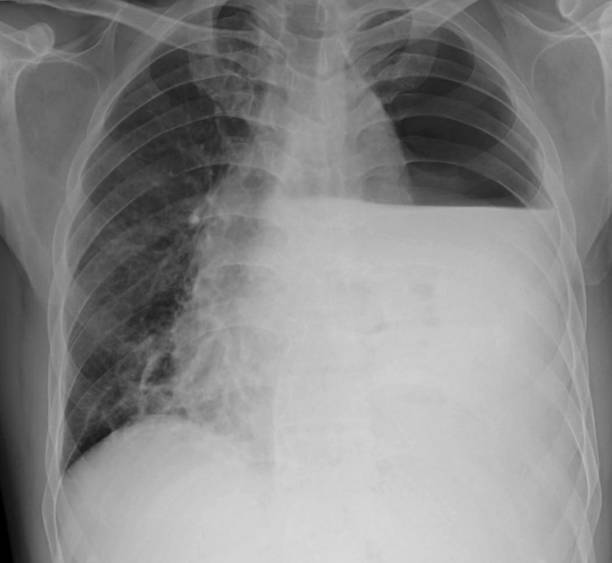

흉부 X선 검사

기흉이 의심되는 환자에게는 흉부 X선 검사를 실시하여 기흉이 있는지 확인할 수 있습니다. 이 방법은 비교적 쉽고 빠르게 기흉을 진단할 수 있습니다.